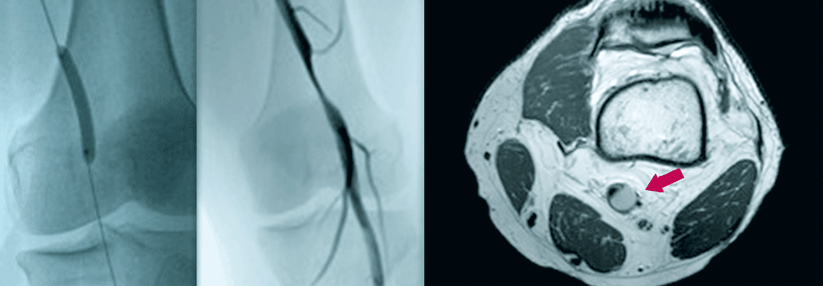

Adventitiazysten beklemmen die Arteria poplitea

Sie haben einen Patienten mit Claudicatio inter­mittens der Wade vor sich, können eine Arteriosklerose aber ausschließen? Dann sollten Sie nach…

Angiologie